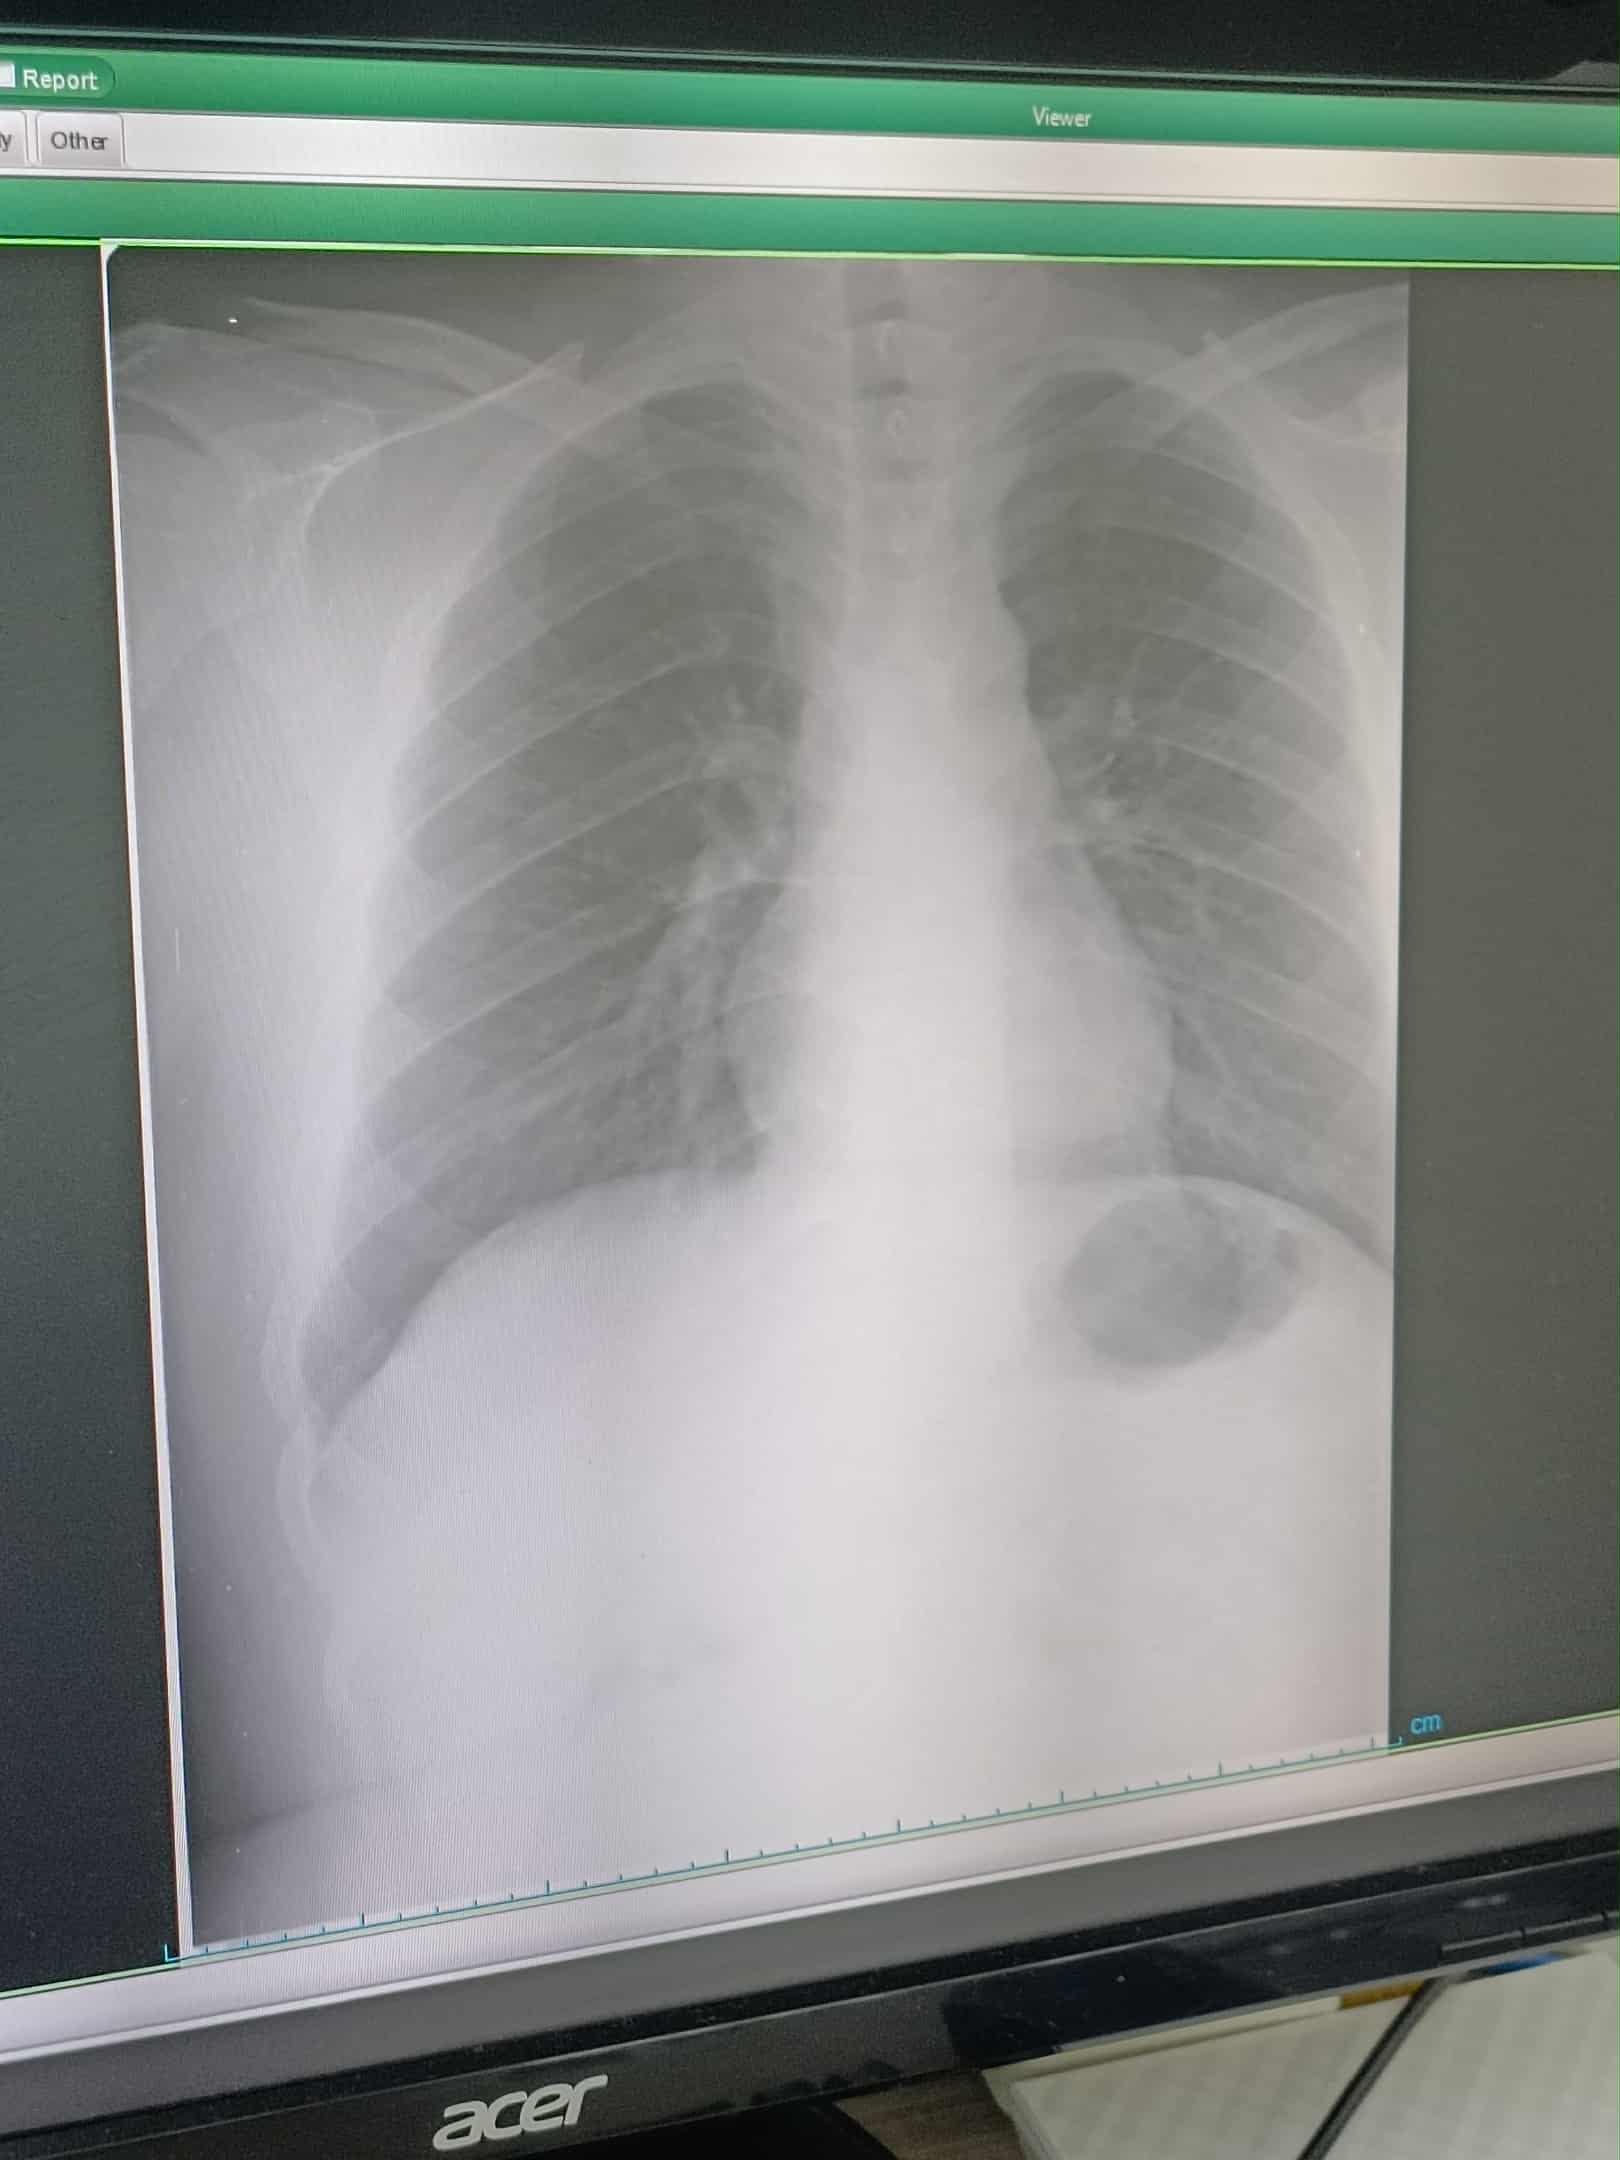

ลูกชายอายุ20กว่าๆ ชอบบ่นว่าหายใจเข้าไม่สะดวก

รู้สึกเหมือนมีอะไรติดตรงหลอดลม

คือมีอาการมาเป็นเดือนแล้วค่ะ ตอนแรกเขาบอกว่าสูดควันเข้าไป แล้วมีอาการตั้งแต่นั้นมา

เราพาไปหาหมอ หลายคลินิคแล้วค่ะ บางที่ก็ว่ากรดไหลย้อน ให้ยามาก็ไม่ดีขึ้น

บางที่ก็ว่าแพนิค บางที่ก็พ่นยาให้

เว้นระยะมาเป็นเดือนวันนี้มาบ่นอยากไปหาหมออีก เพราะไม่หาย

เราควรพาไปพบแพทย์แบบไหนดีค่ะ หูคอจมูก หรือเข้า รพ.เอกชนไปเลย

เอ็กซ์เรย์ปอดก็แล้ว ตรวจคลื่นหัวใจก็แล้ว 😵😵